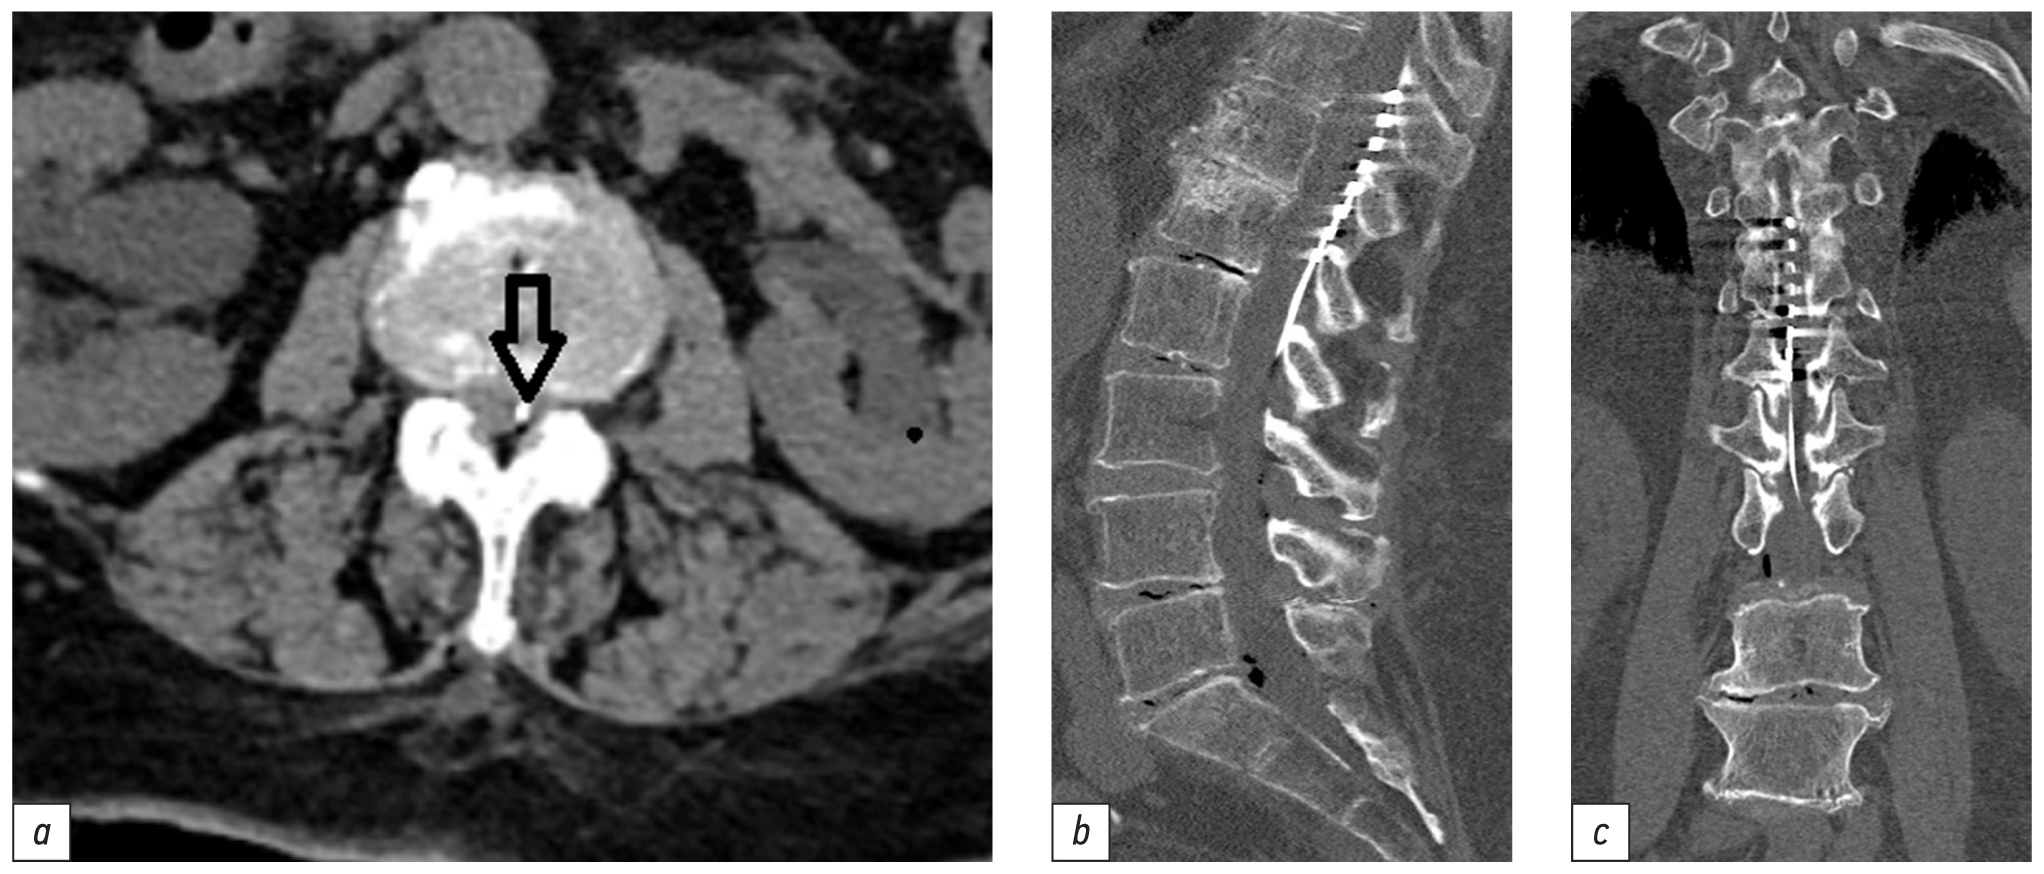

При контрольной КТ пояснично-крестцового отдела позвоночника между остистыми отростками L2 и L3 позвонков парасагиттально слева заведён эпидуральный электрод, расположенный в заднем эпидуральном пространстве. Восьмиконтактный электрод расположен на уровне Th10–Th12 позвонков в задних отделах позвоночного канала, его дистальный конец ― на уровне Th10 позвонка (рис. 3).

Рис. 3. Компьютерная томограмма пояснично-крестцового отдела позвоночника после установки спинальных электродов на уровне Th12–L1 позвонков: а ― электрод в заднем эпидуральном пространстве между остистыми отростками L2 и L3 позвонков (стрелка); b ― электрод в заднем эпидуральном пространстве на уровне Th12–L1 позвонков; с ― расположение электрода в заднем эпидуральном пространстве. / Fig. 3. Computed tomography of lumbosacral spine after epidural electrode implantation at the Th12–L1 level (constant neuromodulation): а ― electrode is placed in posterior epidural space, insertion point is midline between L2 and L3 spinous processes (arrow); b ― electrode is placed in posterior epidural space at the Th12–L1 levels; с ― location of the electrode in the posterior epidural space.

На вторые сутки после имплантации пациентке была начата нейростимуляция спинного мозга в циклическом режиме Burst с частотой 40 Гц, шириной импульса 1000 мкс, амплитудой 0,60–4,05 мА; заряд электрода (--+00000). Значение импеданса составило 337 Ом для данной программы. На третьи сутки после имплантации нейростимулятора болевой синдром уменьшился, пациентка поэтапно вертикализирована и активизирована в пределах палаты. Для коррекции параметров стимуляции пациентка была обучена обращению с пультом. На 13-е сутки от момента госпитализации больная выписана из стационара домой в удовлетворительном состоянии.